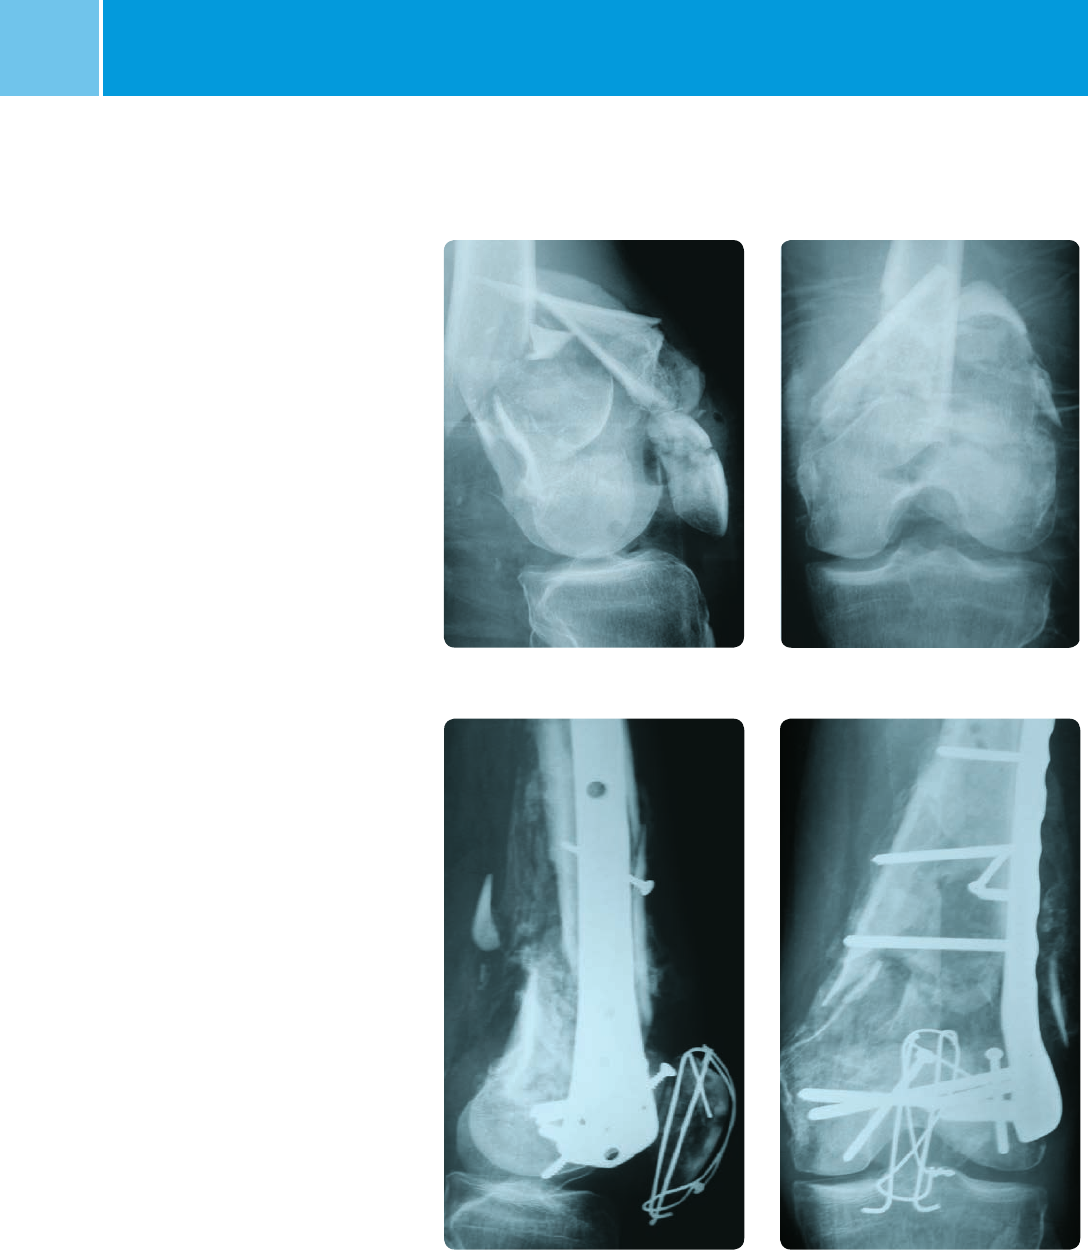

Case 2: Intra-articular fracture

Lateral view preoperative AP view preoperative

Lateral view postoperative AP view postoperative